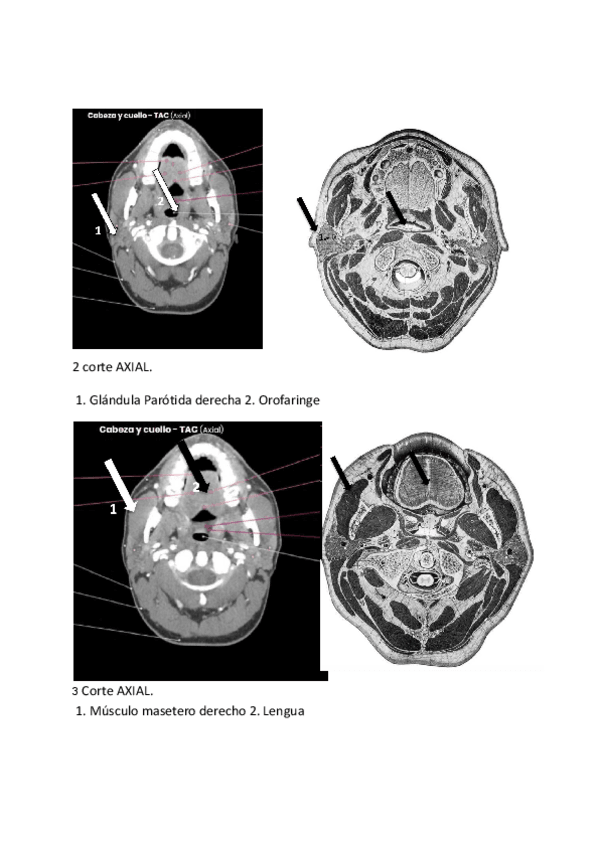

He publicado nuevos practicas de 2º Anatomía: sangre, sistema cardiovascular y respiratorio: Practica-Aplicaciones-readiologicas.pdf